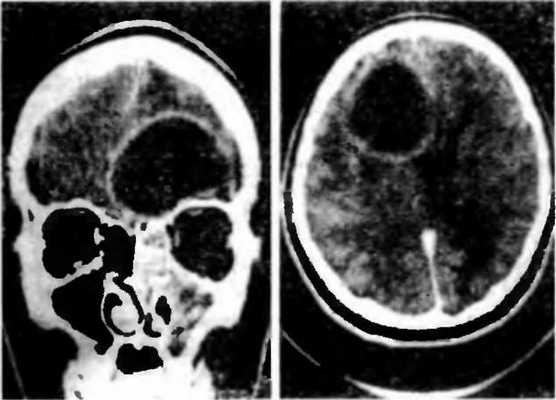

Точность диагностирования с помощью КТ головного мозга зависит от стадии формирования абсцесса. На ранних стадиях заболевания диагностика затруднена. На этапе раннего энцефалита (1-3 сутки) КТ определяет зону сниженной плотности неправильной формы. Введенное контрастное вещество накапливается неравномерно, преимущественно периферических отделах очага, реже в центре.

На более поздних этапах энцефалита контуры очага приобретают ровные округлые очертания. Контрастное вещество распределяется равномерно, по всей периферии очага; плотность центральной зоны очага при этом не меняется. Однако на повторной КТ (через 30-40 минут) определяется диффузия контраста в центр капсулы, а также наличие его и в периферической зоне, что не характерно для злокачественных новообразований.

Инкапсулированный абсцесс мозга на КТ имеет вид округлого объемного образования с четкими ровными контурами повышенной плотности (фиброзная капсула). В центре капсулы зона пониженной плотности (гной), по периферии видна зона отека. Введенное контрастное вещество накапливается в виде кольца (по контуру фиброзной капсулы) с небольшой прилежащей зоной глиоза.

На повторной КТ (через 30-40 минут) контрастное вещество не определяется. При исследовании результатов компьютерной томографии следует учесть, что противовоспалительные препараты (глюкокортикостероиды, салицилаты) в значительной степени влияют на скопление контраста в энцефалитическом очаге.